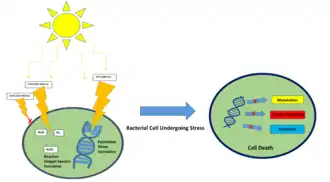

Reactive oxygen species (ROS) are an essential component of SDT as they provide the cytotoxicity of sonodynamic therapy; they are produced when ultrasound is coupled with a sensitizing drug and molecular oxygen.[1] Without ultrasound, the drug is not toxic. However, once the drug is exposed to ultrasound and molecular oxygen, it becomes toxic.[1] Photodynamic therapy, from which sonodynamic therapy was derived, uses a similar mechanism. Instead of ultrasound, light is used to activate the drug.[1] SDT allows the ultrasound to reach deeper into the tissue (to about 30 centimeters) compared to photodynamic therapy (PDT) since it can be highly focused.[1] This increased penetration depth ultimately means that SDT can be utilized to treat deeper, less accessible tumors and is more cost-effective than PDT.[6][1] Photodynamic therapy can be used in combination with sonodynamic therapy and is expanded upon in the Applications section of this article. Sonodynamic therapy can be used synergistically with other therapeutic methods such as drug-loaded microbubbles, nanoparticles, exosomes, liposomes, and genes for improved efficacy. Currently, SDT does not have any clinical products and acts as an adjuvant for the aforementioned therapeutic methods, but it has been explored for use in atherosclerosis and cancer treatment to reduce tumor size in breast, pancreas, liver, and spinal sarcomas. [7][3] [8][9][10] [11][12][13] [14][15][16]

The mechanism of action for sonodynamic therapy is the use of low-intensity ultrasound through the use of focused mechanical waves to create a cytotoxic effect. However, SDT itself is non-thermal, non-toxic, and is able to non-invasively penetrate deep into tissue compared to other delivery methods such as photodynamic therapy. SDT is often performed alongside the use of a sonosensitizer such as porphyrin, phthalocyanines, xanthenes, and antitumor drugs.[17] Ultrasound waves are also classified as acoustic waves, and the effect they have on the tissue of application can be described by a process called cavitation. Cavitation occurs as a specific interaction between ultrasound and aqueous surroundings and causes gas bubbles to break upon exposure to particular ultrasonic parameters, thus promoting penetration of the therapeutic into the biological tissues by generating cavities near the edge of the membrane.[18][1] Cavitation can be broken down into stable and inertial cavitation. In stable cavitation, the oscillation of gas bubbles causes the environmental media to intermix.[1] In inertial cavitation, gas bubbles increase in volume and almost reach their resonance volume, swelling before aggressively collapsing.[1] The implosion of vesicles results in a drastic temperature and pressure change, thereby increasing the cell membrane's permeability to various drugs.[1][19] Microbubbles are created by the acoustic waves from the ultrasound that expand and collapse, releasing energy, bringing the sonosensitizer into an excited state, and generating a ROS. The cavitation of this gas bubble can form the ROS with different methodologies such as sonoluminescence and pyrolysis.[1] Apoptosis results from the formation of ROS and mechanical forces of SDT through membrane disruption in a process called lipid peroxidation. Necrosis is also a potential result of SDT.

The influence of sonoluminescence on SDT and ROS has not been fully elaborated within literature.[1] Currently, it is understood that sonoluminescence allows the emission of light upon bubble collapse which can activate sensitizers. A study by Hachimine et al. highlights the use of SDT as a method to activate a low photosensitive sonosensitizer, DCPH-P-Na(I), for cancer that is too deep within the tissue to combat utilizing PDT without skin irritation.[1][20] Pyrolysis raises the surrounding temperature, enhances the cavitation process, breaks down the sensitizer, generating free radicals, and the free radicals interact within their environment to generate ROS.[1] For both methods, the importance of the singlet oxygen compared to the hydroxyl radical to induce cytotoxicity has been highlighted.[1][20][21] While other studies[1][22][23] have found the singlet oxygen to not have a substantial effect. Overall, both of these methodologies lack significant breadth in literature to fully explain their role in ROS formation. However, literature has shown success in their analysis and application.[1][4][24]

Two primary mechanisms of ROS generation exist in sonodynamic therapy: sonoluminescence and pyrolysis.[1] Sonoluminescence occurs when ultrasound produces light after irradiating an aqueous solution[1][25] The exact mechanism with which light is produced remains unclear. However, it is suggested that inertial cavitation is a key element for this process.[1][26] Other studies also indicate the potential role of stable cavitation[1][27]

Pyrolysis is believed to occur when inertial cavitation induces an extreme temperature increase, degrades the sonosensitizers, thus producing free radicals that can react and ultimately produce ROS necessary for SDT.[1][28] The localized temperature increase assists in the inertial cavitation and breakdown of the sonosensitizer in order to create ROS. The pyrolysis within the cavitation bubbles will produce H+ and OH- via weak bonding within the solute molecule.[1][19]